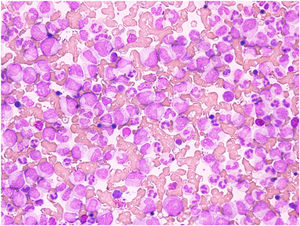

At 25 years of age, he presented with epistaxis. On evaluation, his Hb was 11 g/dL, total leukocyte count (TLC) 527,000 /mm3 and a peripheral blood smear was suggestive of myeloproliferative neoplasm, likely CML – chronic phase. (Figure 2 shows the peripheral blood smear with blasts suggestive of CML). He was positive for the breakpoint cluster region-Abelson oncogene (BCR-ABL) rearrangement with a major translocation (P210 (e13a2, e14a2) and initiated imatinib treatment. After three months, his Hb level had dropped to 8.5 g/dL. Mutational analysis revealed the alpha thalassemia mutation-heterozygous deletion (-α 3.7α/αα or αα/-α3.7α). No Beta thalassemia mutation was detected. Furthermore, next generation clinical exome sequencing detected ‘Heterozygous’ variants in the PKLR gene (compound heterozygous, viz. NM_000298.5:c.1456C>T;p.Arg486Trp and NM_000298.5: c.1178A>G; p.Asn393Ser) Table 1 .